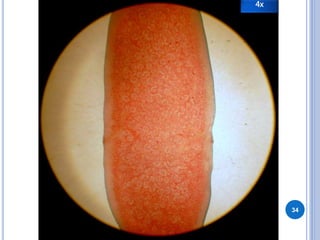

Este documento describe las características generales y las etapas del ciclo de vida de Dipylidium caninum. Explica que la larva cisticercoide es la etapa infectante, mientras que las proglótides en las heces son la etapa diagnóstica. Se transmite por la ingestión de pulgas infectadas y se diagnostica mediante una prueba de lugol en las heces. El huésped definitivo es el perro y los huéspedes accidentales son las ratas y los humanos.